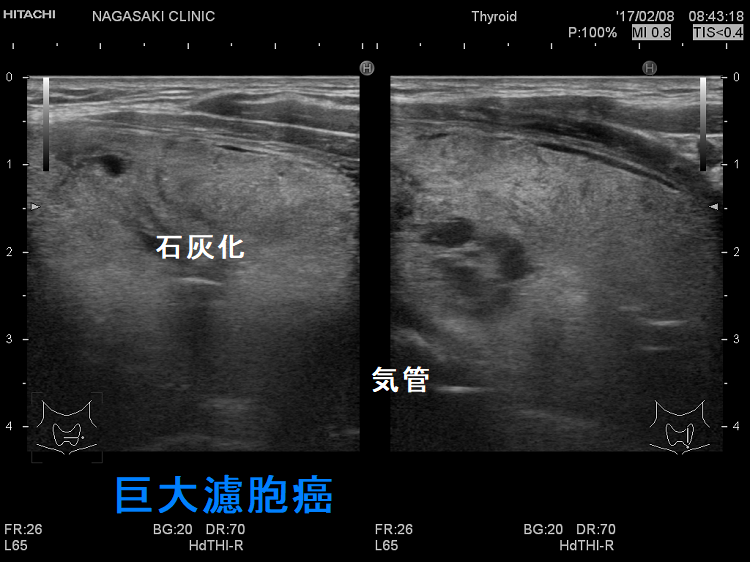

巨大甲状腺腫や高度肥満による気道狭窄で甲状腺切除手術の気道確保困難(挿管困難)が予測される場合、VV-ECMO(体外式膜型人工肺)開始後、気管支鏡を用い挿管。内臓逆位では心血管・消化器系の奇形を合併しなくても左右の反回神経の走行が逆になるため注意。巨大甲状腺腫、甲状腺癌の転移・浸潤が胸骨に及ぶ場合、胸骨切開(全切開、部分切開)/胸骨切除が必要。甲状腺手術の皮膚縫合は美容上の問題から形成外科が行う事も。甲状腺の病気があれば経皮経食道胃管挿入術(PTEG/ピーテグ)は禁忌。海外では甲状腺摘出術後の頸部創傷治癒促進と瘢痕形成抑制にPRP療法。

巨大甲状腺腫、甲状腺腫瘍や高度肥満による気管の圧迫・気道狭窄(最狭窄部1cm以下)のため、甲状腺切除手術における気道確保困難(挿管困難)が予測される場合、

甲状腺機能亢進症/バセドウ病の巨大甲状腺腫による上気道狭窄で吸気時喘鳴(ストライダー;上気道・中枢気道狭窄による喘鳴)

甲状腺手術で首の辺を切開するのは当然ですが、胸骨切開(全切開、部分切開)/胸骨切除が必要な時もあります。

- 縦隔進展する巨大甲状腺腫(縦隔内甲状腺腫 )

- 甲状腺癌の転移・浸潤が胸骨の所まで及ぶ